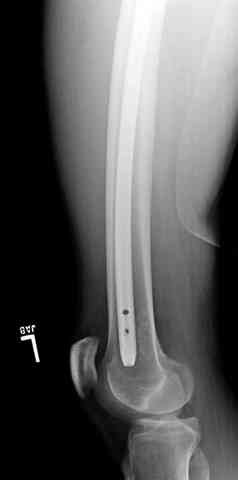

1 Проксимальный перелом бедра, антеградный гвоздь

Для фиксации огнестрельных переломов бедра и длинных костей предпочтение отдаем интрамедуллярному методу фиксации, о котором еще в 1993 году написали Bergman M. Tornetta P. Kerina M. Sandhu H. Simon G. Deysine G. Journal of Trauma. [JC:kaf] 34(6):783-5